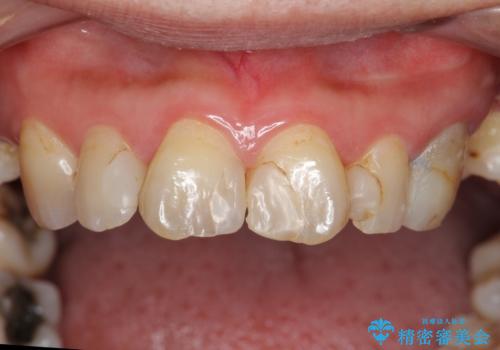

前歯の虫歯 つぎはぎの歯をセラミックに

- 矯正治療後に、前歯の樹脂の詰め物のやりかえを提案していましたが、治療は当時行いませんでした。

その後3年間来院がなく、その間に前歯の虫歯の進行があり、治療を行いました。

やはり、樹脂で虫食い状になってしまうと虫歯が進行しやすくなっているためクラウンがおすすめです。